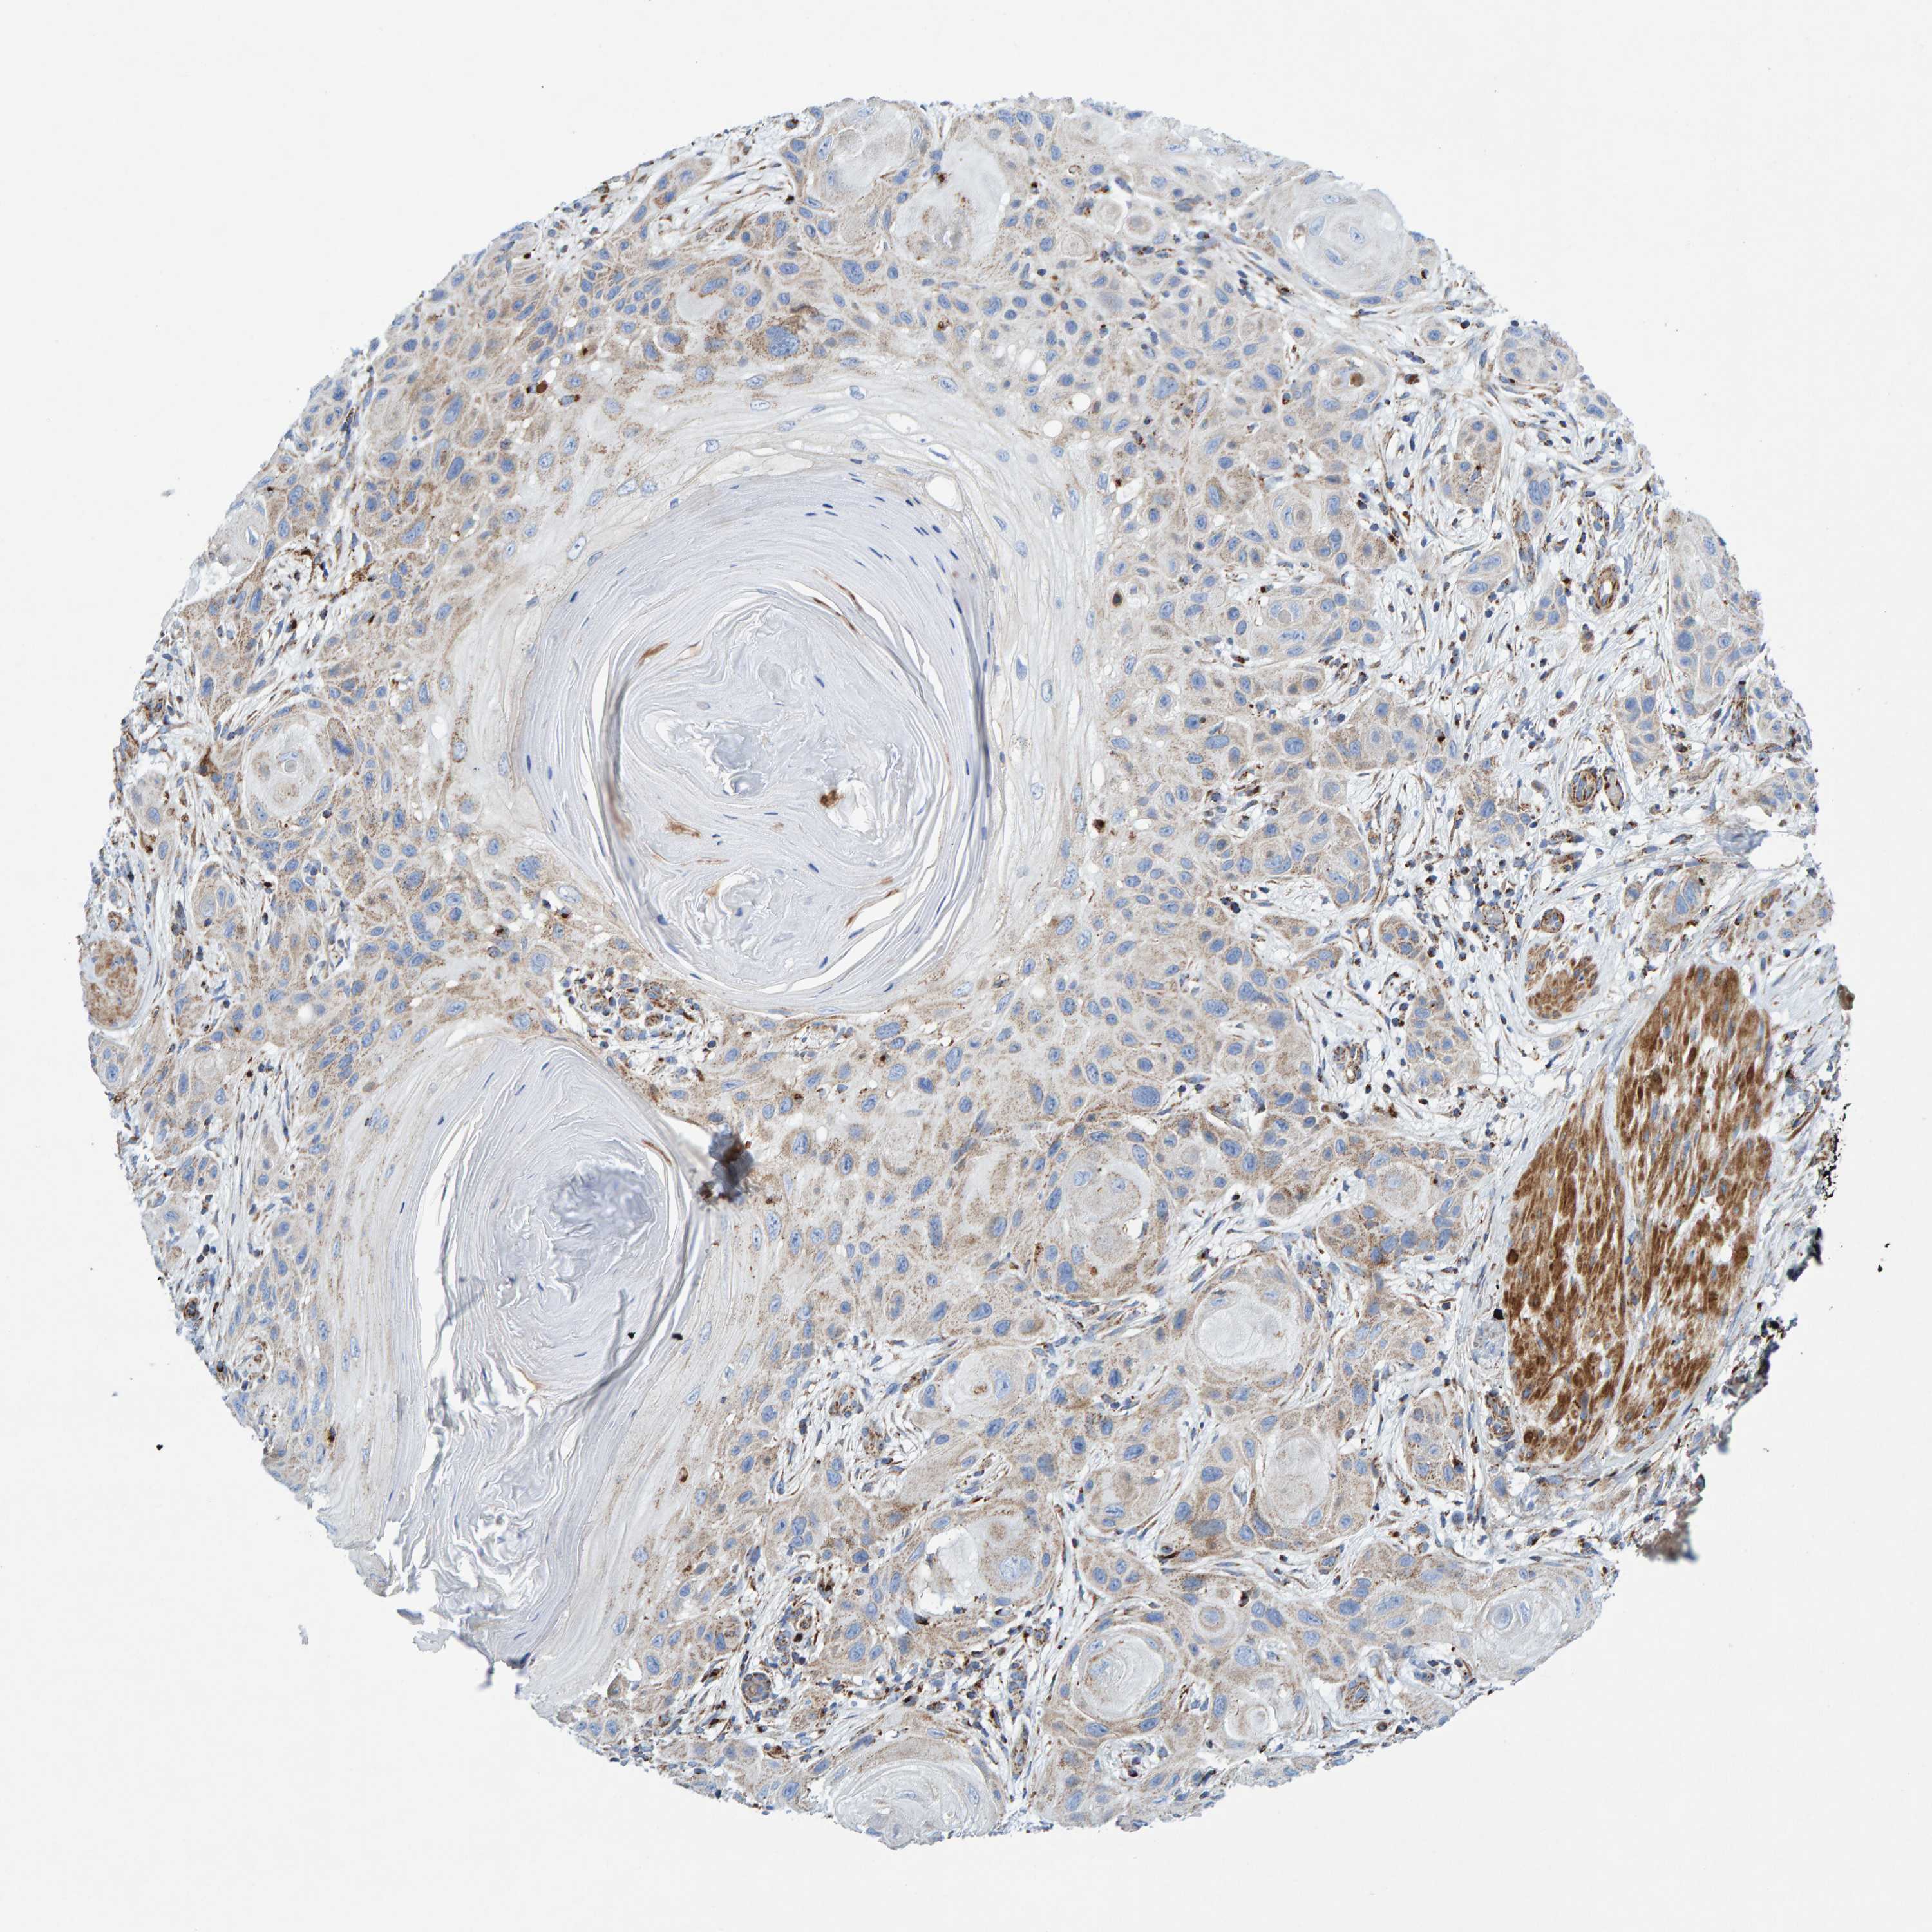

SKIN CANCER - Protein expressioni

A mouse-over function shows sample information and annotation data. Click on an image to view it in a full screen mode. Samples can be filtered based on level of antibody staining by selecting one or several of the following categories: high, medium, low and not detected. The assay and annotation is described here.

Antibody stainingi

Antibody staining in the annotated cell types in the current human tissue is reported as not detected, low, medium, or high, based on conventional immunohistochemistry profiling in selected tissues. This score is based on the combination of the staining intensity and fraction of stained cells.

Each image is clickable and will lead to virtual microscopy that enables deeper exploration of all samples and also displays staining intensity scores, fraction scores and subcellular localization as well as patient and tissue information for each sample.

Antibody HPA023262

Basal cell carcinoma